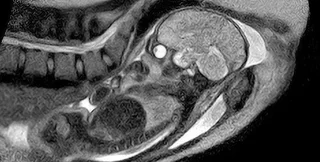

Скани МРТ немовлят виглядають дуже лякаюче | Фото: Twitter

Жахливі знімки можуть здатися кадрами фантастичного фільму про прибульців або демонів, але дослідники запевняють, що вони реальні.

Дивлячись на кадри, легко подумати, що вони взяті з якогось голлівудського науково-фантастичного фільму про прибульців, а можливо навіть фільму жахів. Однак дослідники непохитні: на жаль, скани справжні — саме так виглядає людське немовля в утробі матері, якщо дивитися на нього через МРТ.

Однак МРТ пропонує жахливо деталізовані чорно-білі зображення, які часом ставлять батьків у глухий кут. Якщо ви думали, що на скані МРТ малюк буде дуже чарівним, на жаль, це зовсім не відповідає дійсності.

Вчені розповіли, що МРТ використовує магнітні поля та радіохвилі для отримання докладних зображень внутрішньої частини тіла. Наші очі та мозок мають вищий рівень "сигналу" (радіохвиль), а тому виглядають яскравішими й виділяються на зображеннях. Інші частини тіла випромінюють нижчі рівні, а тому здаються темнішими.